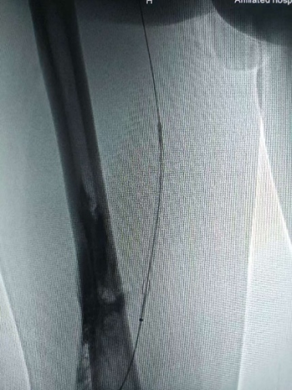

在导丝引导下将抽吸导管送至目标血管位置,抽出部分血栓后,沿导丝置入Tendfast取栓支架至预定位置。回撤输送鞘管释放支架,锁定推送管并调整支架支撑力,使其充分嵌入血栓。当回撤支架至抽吸导管口时,连接负压抽吸装置,在持续负压下缓慢将取栓支架撤出体外。反复多次,拉出大量暗红色血栓,拉栓效果满意。

支架取栓中